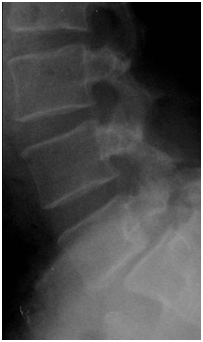

При сравнении рентгенограмм в динамике может быть выявлено увеличение степени спондилолистеза (Рис. №3).

Рис. №3. Рентгенограммы больного Н. А – 2009 год, Б - 2013 год.

1.Обзорная рентгенография.

Рис. №4. Рентгенологическая картина спондилолистеза.

2.Рентгенография с функциональными пробами

Данный метод исследования применяется с целью определения функционального состояния позвоночных сегментов, определения формы спондилолистеза (стабильная, нестабильная). Функциональные рентгенограммы выполняют в боковой проекции в положении максимально возможного сгибания и разгибания (Рис. № 5).

Рис. №5. Определение нестабильности позвоночного сегмента. функциональные рентгенограммы (нестабильность в сегменте L4-5): А – сгибание; Б – разгибание.